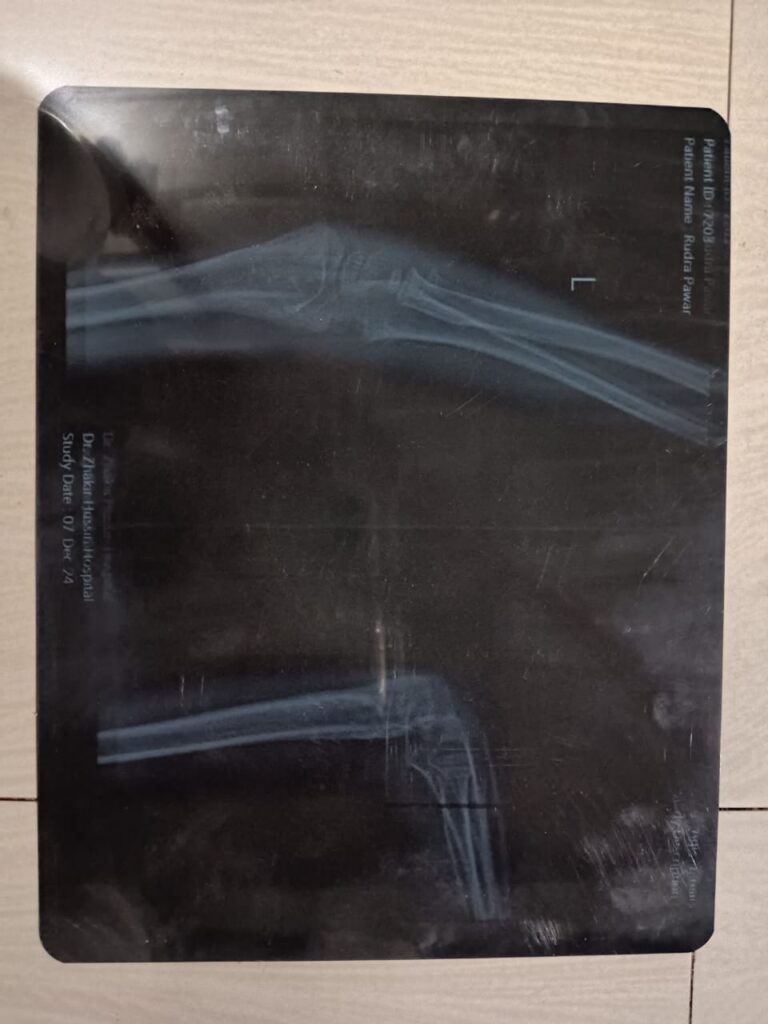

Master Rudra Manoj Pawar

Age:- 7 Year old / Male

Treatment:- Deformity Correction

Estimated Expenditure:- 2,00,000/-